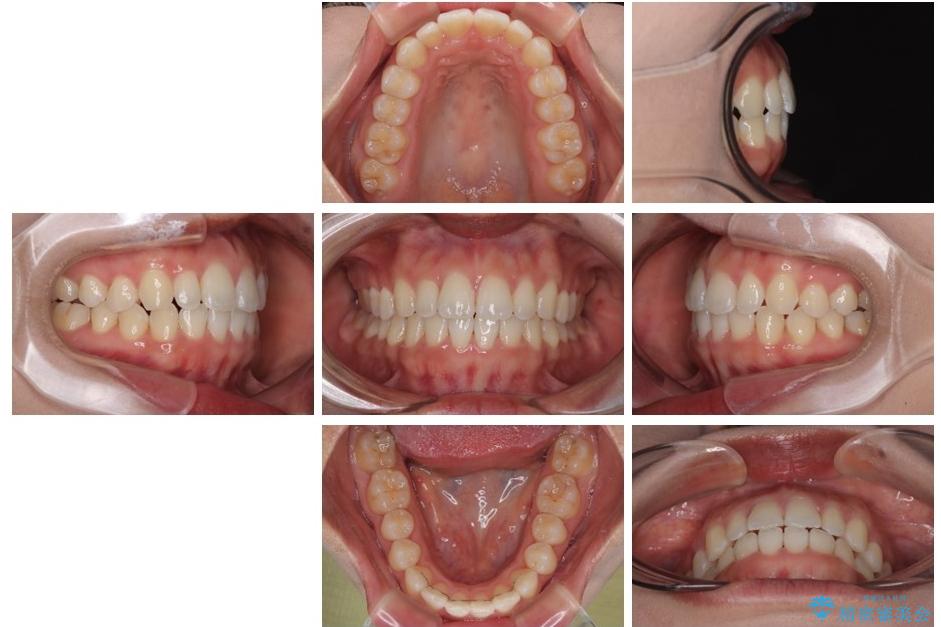

治療後

• 目立ちにくい表側装置で1年完了!狭いアーチを側方拡大し前歯のデコボコを整えた症例 治療後画像

前歯が自然なアーチにきれいに並び、正中(上下の中心線)も整い、咬み合わせも良好です。

側方拡大することで、非抜歯であるにも関わらず前歯が前方に出ることなく、バランスの良い仕上がりとなりました。